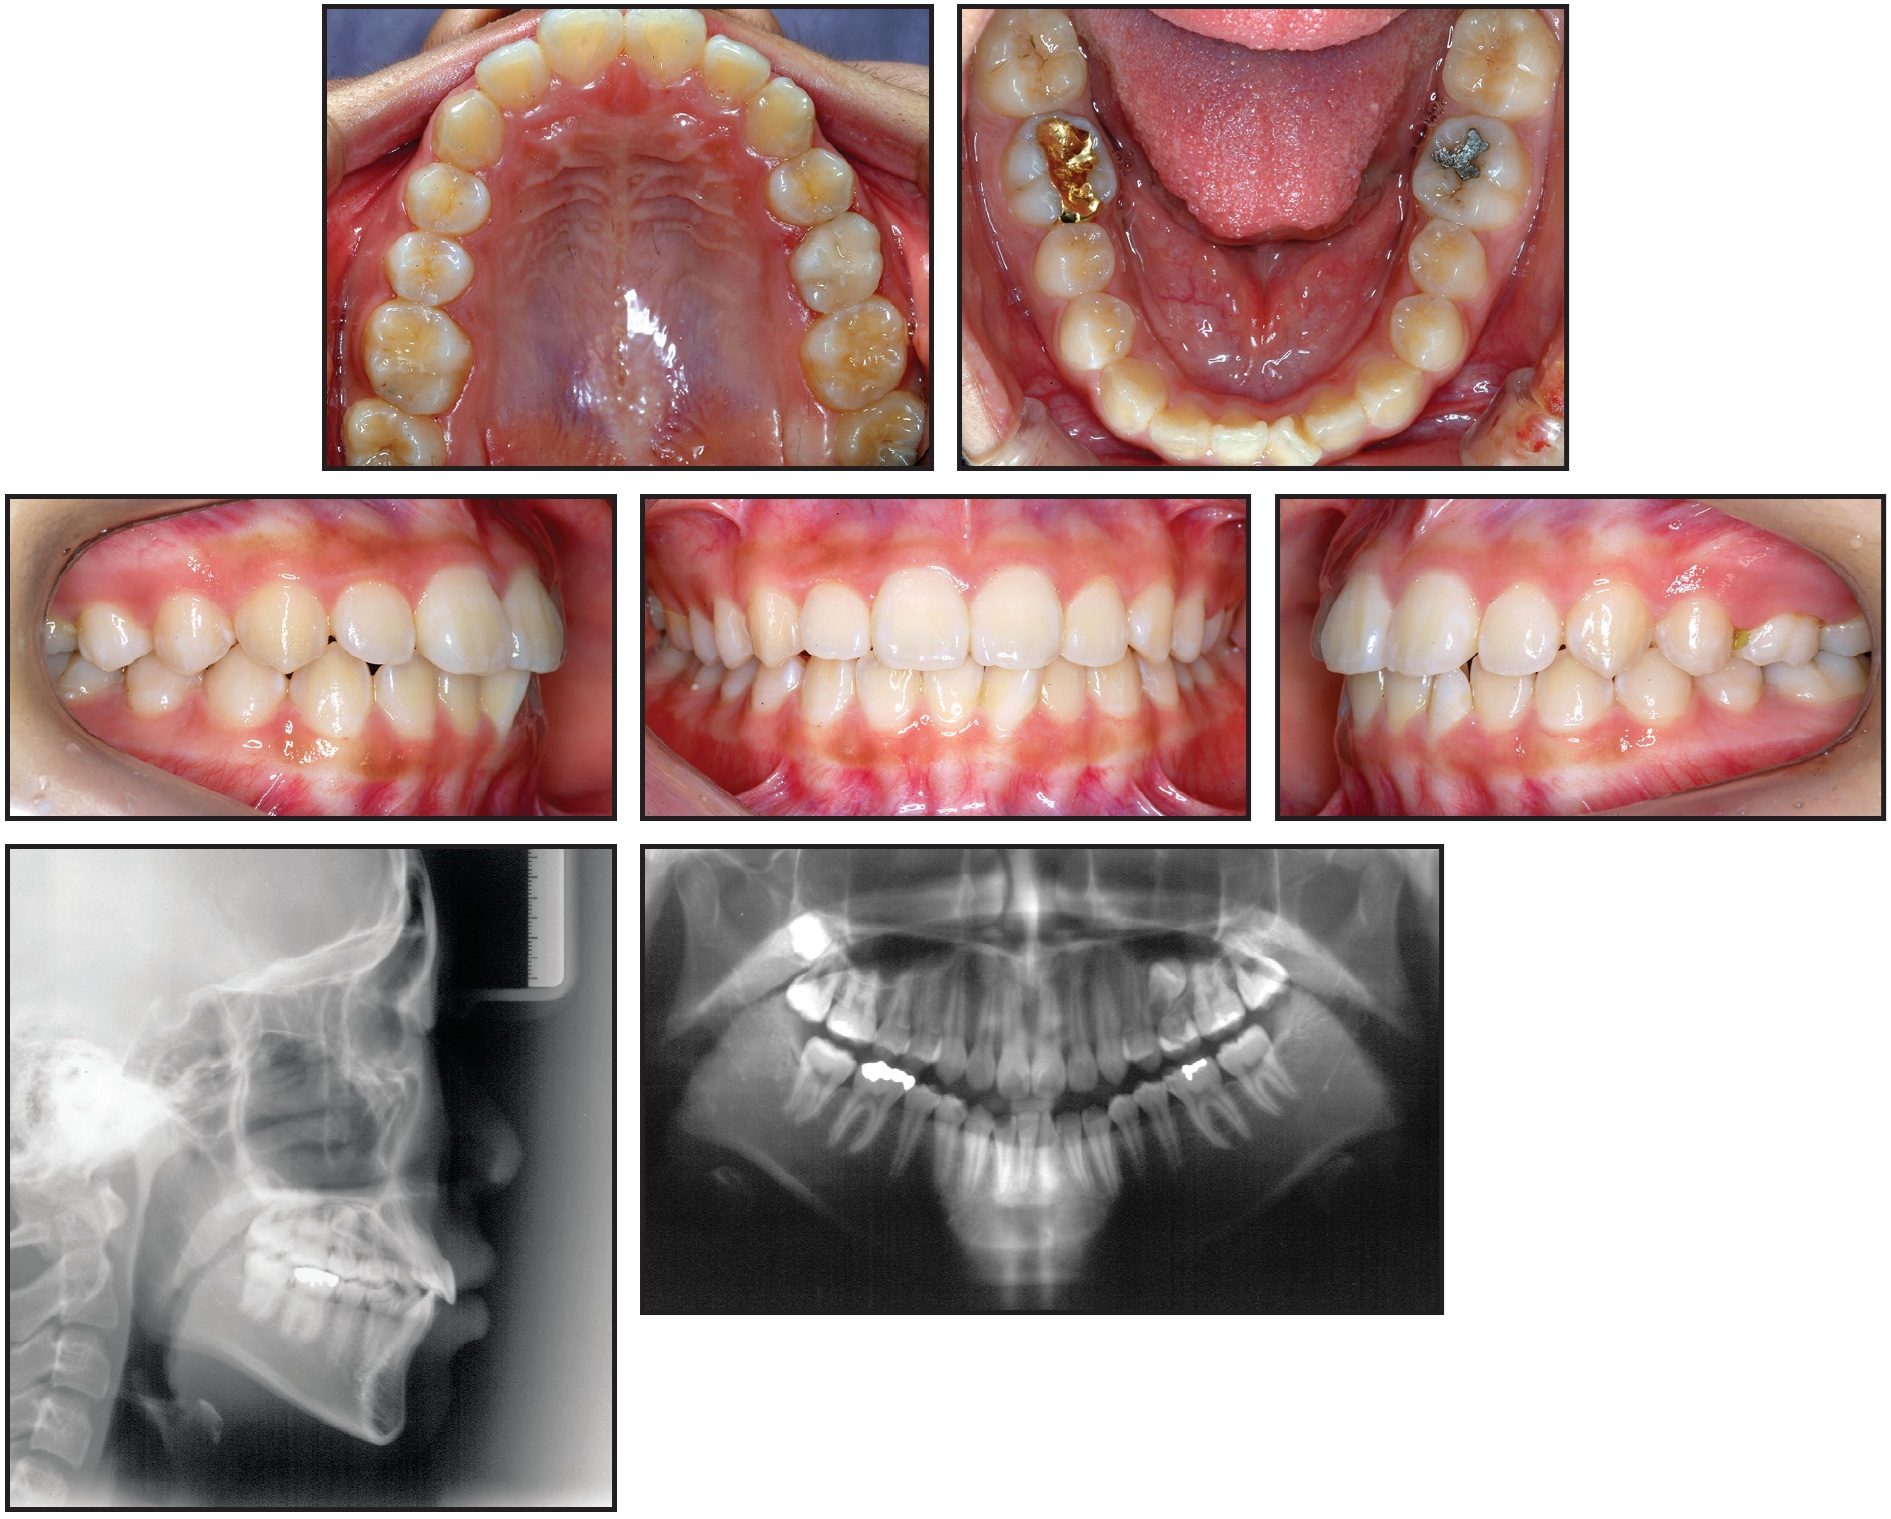

A 14-year-old female presented with the chief complaint of prolonged retention of a second deciduous molar (Fig. 1). She had bilateral Class I canine and molar relationships and a balanced facial pattern. A retained upper left second deciduous molar was found in the position of the missing second premolar. Radiography revealed an impacted and inverted upper left second premolar, with the crown facing toward the maxillary sinus floor.

Fig. 1 14-year-old female patient with prolonged retention of second deciduous molar and bilateral Class I canine and molar relationships before treatment.